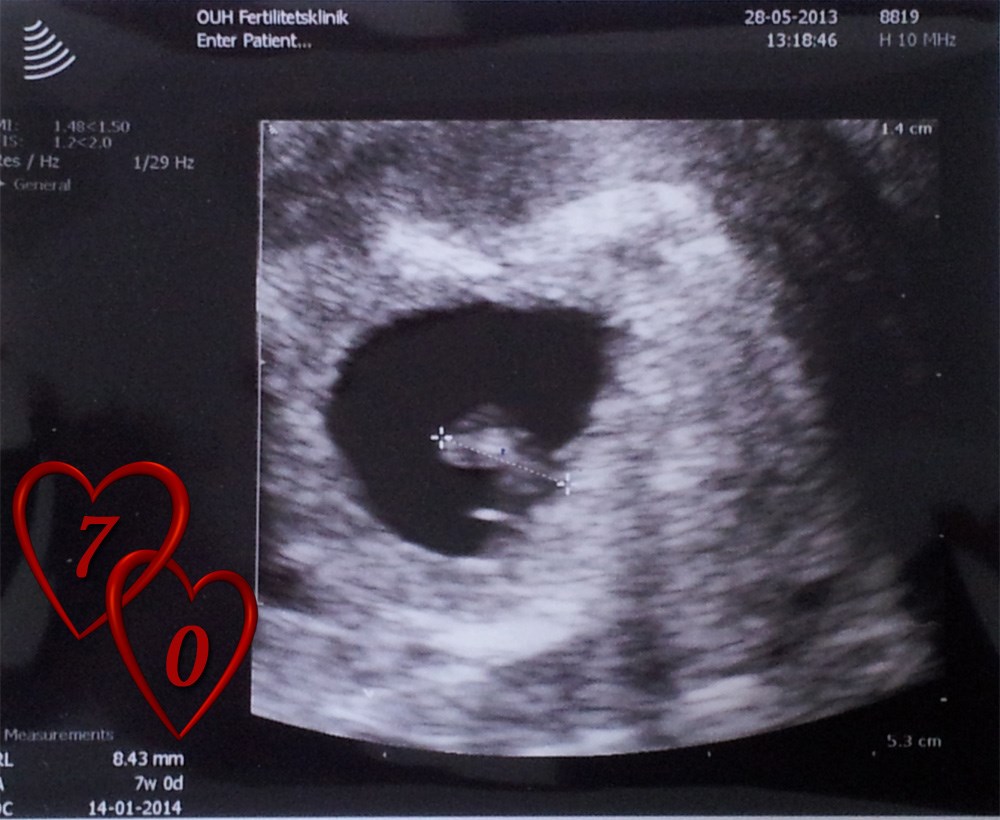

Men altså HCG gav os da et hint, da det var 659

Dog døde den ene i uge 9, så venter kun én lille bebs nu